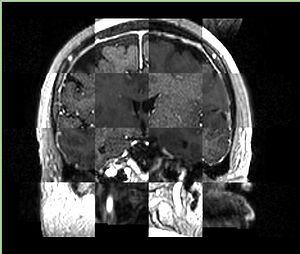

• Checkerboard appearance of unregistered images for the representative data of interest

• Case03

• Case04

• Case10